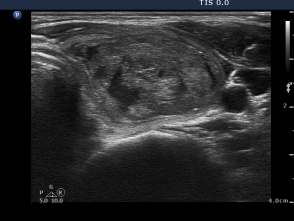

Third session of sclerotherapy (fourth row of images):

The lesion decreased in size. After removal of 2 mL bloody fluid we injected 4 mL ethanol.